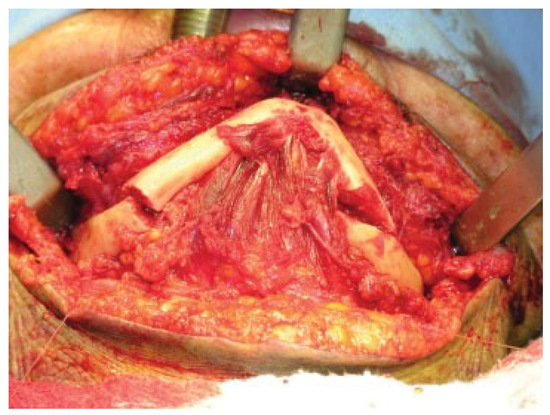

The patient was anesthetized with nasotracheal general anesthesia. Because he didn’t wear dental prostheses in the preoperative period, anatomic reduction of the fractured segments was the treatment of choice. Because the left subcondylar fracture had minimal displacement and did not cause significant mouth-opening limitation, it was not surgically treated. Two independent submandibular approaches were made [14]. The fractures were reduced and stabilized with noncompression 2.4-mm reconstruction plates with bicortical screws (Figure 3 and Figure 4). Plane sutures were performed and compressive dressings applied. No drains were used.

Figure 3. Left side reduced and fixed by a 2.4-mm reconstruction plate.